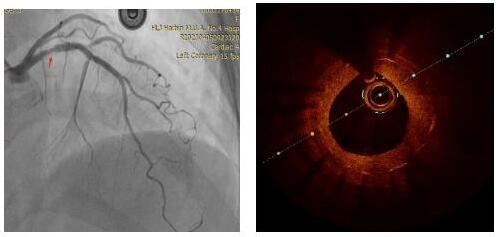

患者为62岁女性,是一位冠状动脉支架术后7年的患者,造影发现该患者冠状动脉前降支支架近端有大约80%的再狭窄,于是采用OCT检查对支架内情况进行测量,发现病变处有严重的狭窄。

对冠状动脉造影及OCT图像进行综合判断,目前已经具备安全进行冠状动脉内激光消蚀的条件,于是在病变处进行激光消融,随后在OCT指导下采用后扩球囊改善贴壁情况,顺利完成手术。